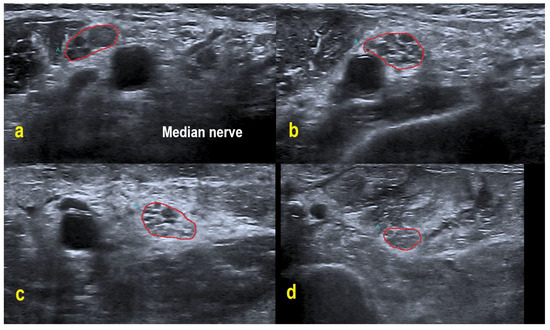

Four CIDP patients and every POEMS syndrome patient showed hypoechoic nerves (class 1), whereas the remaining CIDP patients demonstrated a more heterogeneous pattern with hypo- and hyperechoic fascicles (class 2). No patient exhibited class 3 pattern. In contrast to the patients with CIDP, the examined POEMS syndrome patients featured additional hyperechoic intraneural connective tissue. Figure 3 exemplifies the different HRUS findings.

Therefore, the observed echogenicity patterns in our POEMS patients could be a promising finding. Lucchetta et al. [7] already described hypoechogenic nerves in POEMS syndrome, as was the case in our study. Our POEMS patients presented additional hyperechoic intraneural connective tissue, which is an interesting morphological observation and not known to appear in CIDP. Furthermore, hypoechoic nerves are associated with better treatment response in CIDP (possibly reflecting active inflammation) and can be used as a prognostic marker, while in clinically progressive CIDP, hyperechoic nerves are frequently found (possibly reflecting axonal degeneration [18,21,22]). Follow-up studies have to prove if these findings are applicable to POEMS syndrome patients. The histological correlate behind the increased and hyperechoic interfascicular tissue has to be clarified by histopathological studies in future projects.

Figure 3. HRUS of the right upper arm median nerve. POEMS syndrome patient #1 demonstrated hypoechoic fascicles and hyperechoic intraneural connective tissue ((A) within red border). In CIDP patient #6, HRUS depicted hypoechoic next to hyperechoic fascicles ((B) within red border), whereas HRUS in CIDP patient #9 showed hyperechoic fascicles ((C) within red border).